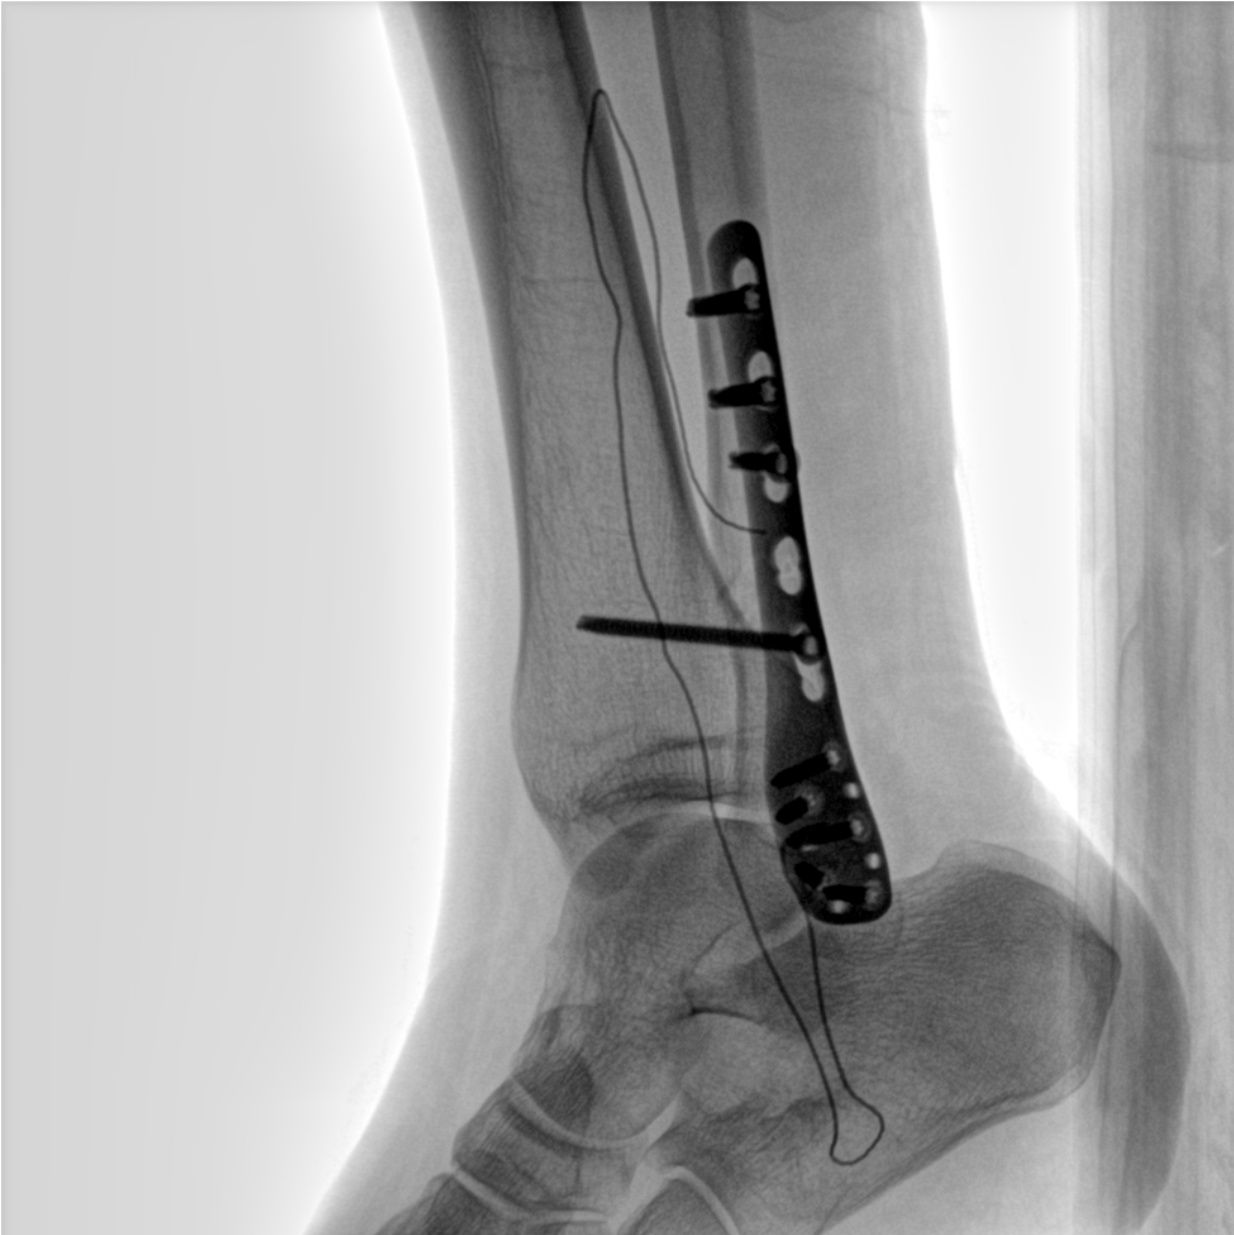

術(shù)中三維成像和橫斷面圖像提供多角度的手術(shù)診斷信息,輔助醫(yī)生進行術(shù)中評估判斷,諸如骨折復位情況和內(nèi)植入螺釘?shù)某叽绾臀恢茫o助手術(shù)更好地完成。